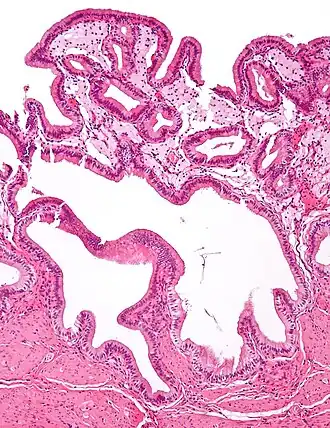

The name strawberry gallbladder comes from the typically stippled appearance of the mucosal surface on gross examination, which resembles a strawberry. The term was coined by surgical pathologist William C. MacCarty of the Mayo Clinic in 1910.[2] Cholesterolosis results from abnormal deposits of cholesterol esters in macrophages within the lamina propria (foam cells) and in mucosal epithelium. The gallbladder may be affected in a patchy localized form or in a diffuse form. The diffuse form macroscopically appears as a bright red mucosa with yellow mottling (due to lipid), hence the term strawberry gallbladder. It is not tied to cholelithiasis (gallstones) or cholecystitis (inflammation of the gallbladder).[3]

Additional images